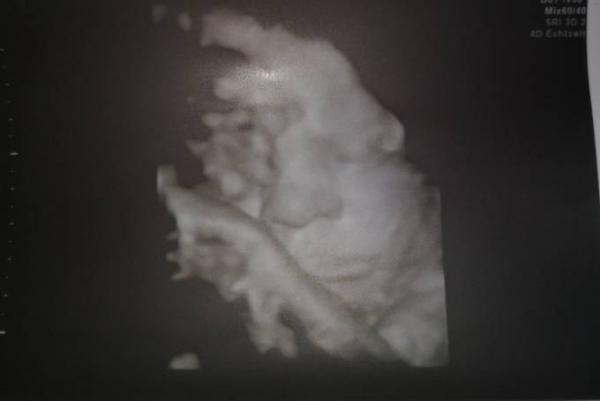

Und ich bin soooo verliebt in die kleine! Alles soweit okay, sie liegt weiterhin in SL und wiegt derzeit ca. 3 kg. Bin echt gespannt wann es soweit ist.

Bild zu Zurück vom FA - Forum für April - Mamis

Das ist ja ein süßes Bild Freut mich das die kleine gesund und munter ist.